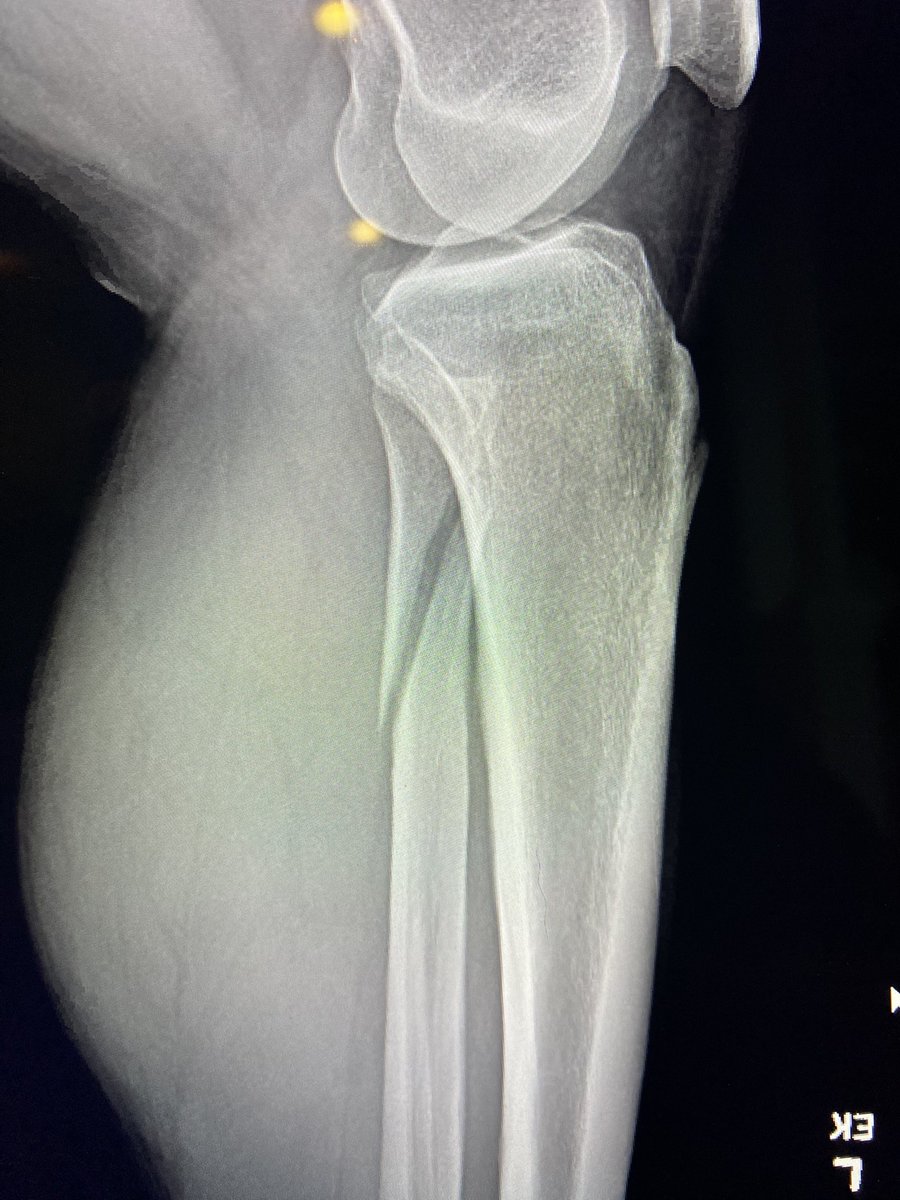

58 male fall from height last week !

Hx: HTN , CAD

Medicine :Aspirin 81 , Clopidogrel

When I aspirate hematoma there was about 6 ml blood

this is the pre_after reduction and the follow up today

He is not elderly in shape and body he looks like 40 !

1/2

@#orthotwitter